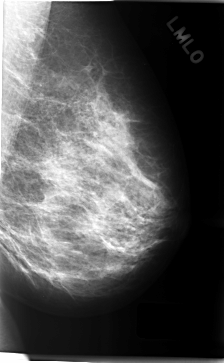

C_0309_1.LEFT_MLO

LEFT_MLO LINES 4712 PIXELS_PER_LINE 2904 BITS_PER_PIXEL 12 RESOLUTION 50 NON_OVERLAY